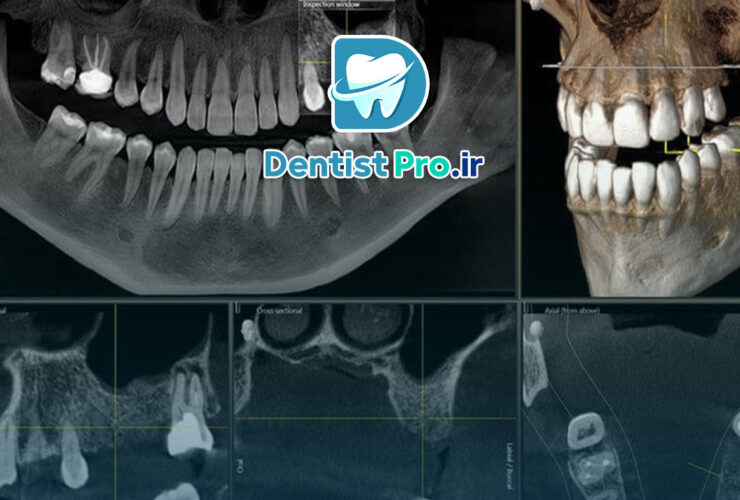

ارتودنسی با تکنولوژی CBCT یکی از جدیدترین و پیشرفتهترین روشهای درمانی در علم دندانپزشکی است که به کمک آن میتوان ...